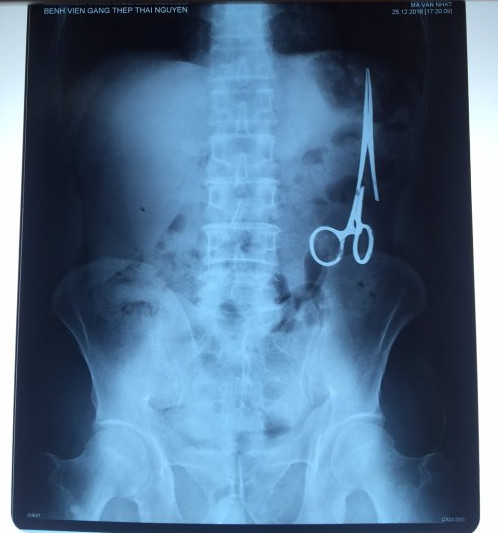

遺留在病人腹中的剪刀

醫(yī)務人員表示,這把剪刀遺留在病人腹部左側,與結腸緊挨著。剪刀的把手已經(jīng)生銹,部分器官也已經(jīng)與剪刀粘連起來。但在過去多年中,M.V.N沒有任何不適感覺,也從未因為留在腹中的剪刀引發(fā)的相關問題去看過醫(yī)生。直到2016年12月,M.V.N因為遭遇了一場車禍,才到鑄鋼醫(yī)院進行身體檢查。

超聲波檢查顯示,M.V.N的腸子中有個奇怪物體,看起來就像醫(yī)用剪刀。M.V.N證實,他曾于1998年6月份在北江省綜合醫(yī)院接受手術,在此后也從未進行過任何手術。近來,他感到腹部有些疼痛,并試圖通過服用藥物治療。12月27日,M.V.N回到北江省綜合醫(yī)院再次進行超聲波檢查,顯示其腹部的確存在怪異物體。